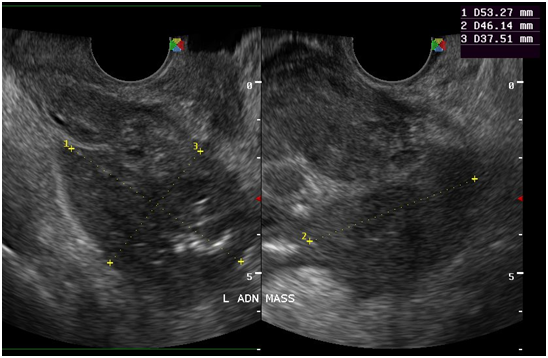

Figure 10 At the left adnexal area is an irregular tubular hyperechoic structure with scattered echogenic stipplings within.

Tuberculous peritonitis is a variant of genital tract tuberculosis. Fallopian tube/uterine disease and tuberculous peritonitis can and does coexist in up to 50% of the cases.22 Tuberculosis is primarily an infection of the respiratory tract. Female genital tuberculosis can develop from a pulmonary nidus of infection or by hematogenous dissemination of organisms and their subsequent localization within the fallopian tube. When the gastrointestinal tract is the portal of infection, involvement of the ileocecal region permits lymphatic spread–primarily to the right fallopian tube.22 The sono graphic findings of this patient described a 5.3x4.6x3.8 cm tubular adnexal mass with scattered echogenic stipplings within, which probably represented tuberculous salpingitis. Myometrial involvement in this patient appeared as irregular scalloping at the periphery of the surrounding hypoechoic myometrium, giving it a marblelized appearance. Dissemination of disease from the fallopian tube occurs by continuous spread to potentially involve the ovary and retrograde into the uterus. Uterine extension involves primarily the endometrium with, at maximum, a 20% incidence of myometrial involvement.22